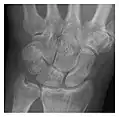

High-energy trauma fractures

Figure 3: A 26-year-old man presenting with wrist pain after being assaulted. (a) Initial anteroposterior radiograph shows a subtle linear lucency within the scaphoid extending to the scaphocapitate articular surface that was overlooked (arrow). (b) Initial "scaphoid" view was negative. (c) Followup anteroposterior radiographs, 12 days later, shows obvious scaphoid fracture (arrows).[1]